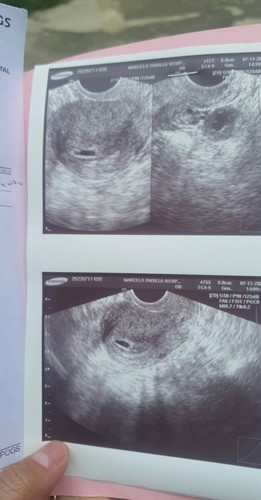

Less than 7weeks

Meron po ba same case ko dito gestational sac plng at less than 7weeks? Pls enlighten me. First time mom po😐#advicepls #firstbaby

Pray lang po, tanging OB nyo lang po makakasagot sa tanong nyo momy, dipo kase bilog yang gestational Sac ninyo meaning possible po na baka walang na buong baby po😢, usually Po pag ganyan 7weeks meron napo Jan makikita lalo na kung TVs😢😢

Unang transV ko po at 5wks, same po yung nakita kasi very early pa. Gest sac and yolk sac palang po kaya pinabalik ako 2 wks later. At 7wks nakita na si baby and may heartbeat na :) at 7-8wks po makikita mo na sya